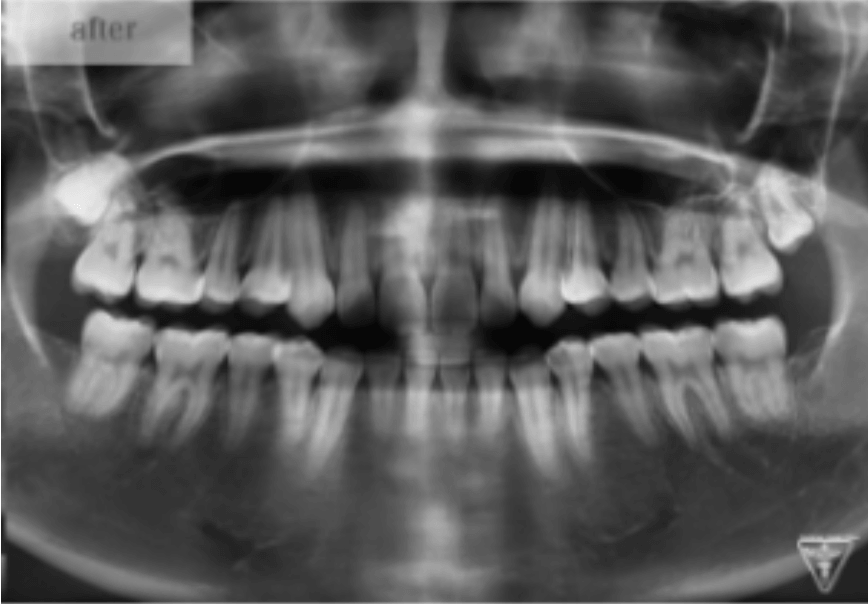

治療後

治療前後の比較